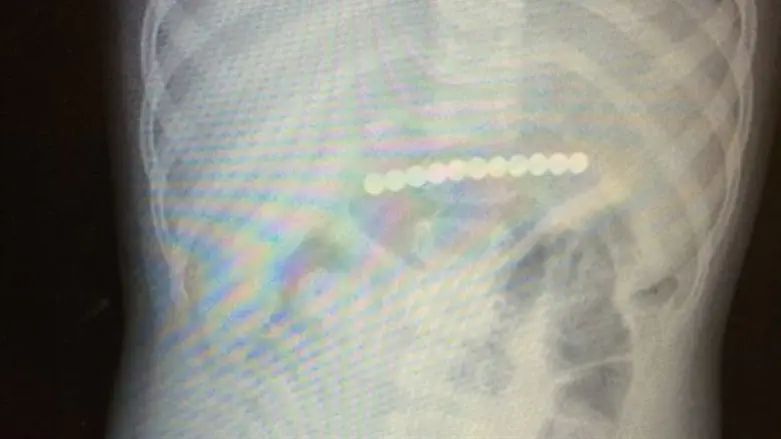

מיד עם קבלתה, נשלחה התינוקת לבדיקת צילום בטן שגילתה כי בבטן העליונה שלה נמצא גוף זר מתכתי מסוג מגנט באורך של 6 ס"מ אותו היא בלעה בשלמותו.

ד"ר שלומי כהן, מ"מ מנהל היחידה לגסטרו ילדים בבית חולים "דנה" סיפר כי "עם קבלת תוצאות צילום הרנטגן, הוזעקתי מביתי חזרה ישירות לחדר הניתוח. כשהיא תחת הרדמה מלאה, ביצעתי בתינוקת אנדוסקופיה של דרכי העיכול העליונות ושלפתי משם כ-11 מגנטים בצורת עיגול צמודים זה לזה לאורכם. מצבה של הילדה טוב וכבר הבוקר היא שוחררה לביתה".